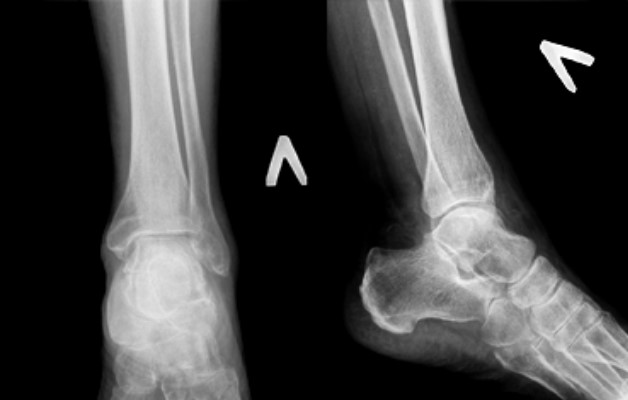

Диагностика и лечение

Диагностика заключается в лабораторных и инструментальных исследованиях. Для подтверждения артрита врач назначает следующие обследования:

- общий и биохимический анализ крови;

- УЗИ;

- рентген сустава;

- МРТ – более информативное исследование, позволяющее рассмотреть мягкие ткани и костные структуры.